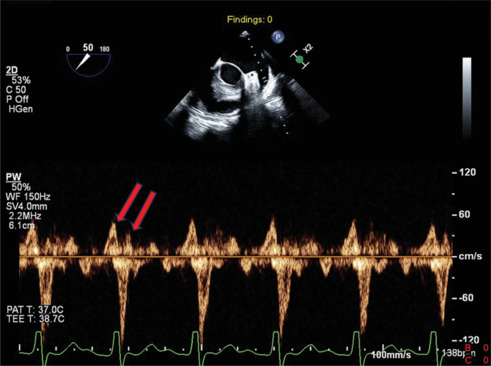

背景:房性心动过速的诊断有时可能具有挑战性。利用超声心动图(主要是经食管超声心动图)评估左心耳(LAA)的多普勒血流模式,是建立心房速性心律失常诊断的有价值的工具,特别是在诊断尚不明确的情况下。结果:该方法简便有效,但在临床实践中应用不足。结论:本文旨在强调结合LAA血流与心电图诊断复杂病例心房速性心律失常的有效性,特别是心房扑动,并鼓励医生采用这种方法更好地识别心房速性心律失常复发和LAA血栓形成的风险患者。

Background: The diagnosis of atrial tachyarrhythmias might be challenging at times. Assessing Doppler flow patterns of the left atrial appendage (LAA) using echocardiography, mainly transesophageal echocardiography, represents a valuable tool for establishing the diagnosis of atrial tachyarrhythmias, especially when the diagnosis remains unclear.

Result: Despite its effectiveness and simplicity, this technique is often underused in routine clinical practice.

Conclusion: This paper aims to underscore the effectiveness of using LAA flow in conjunction with electrocardiograms for diagnosing atrial tachyarrhythmias in complex cases, particularly atrial flutter, and to encourage physicians to adopt this approach to better identify patients at risk for the recurrence of atrial tachyarrhythmias and LAA thrombus formation.